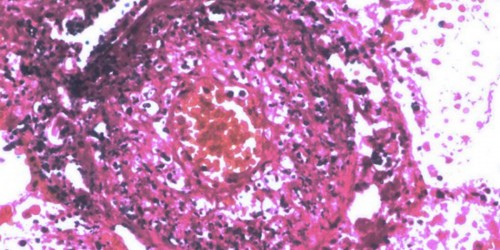

Hi! I guess you've already read it but here's what the only thing I found about it. Since Berger's original paper on mesangial IgA-IgG deposition with hematuria, there have been a number of clinical and pathological studies regarding IgA immune complexes, the mechanisms of glomerular IgA deposition leading to glomerular injury and animal models of IgA nephropathy. During the last quarter of this century, glomerular changes such as IgA nephropathy have also been observed in cases associated with other diseases, such as systemic lupus erythematosus, Schoenlein-Henoch purpura, liver cirrhosis and chronic inflammatory diseases of the lung. This evidence supports the idea of an IgA nephropathy syndrome. On the other hand, IgA is thought to be an important humoral factor at the mucosal immune system and appears to have an antibody function against various etiologic candidates of extrinsic or intrinsic substances at the mucosal and systemic immune system. Glomerular IgA deposition in IgA nephropathy syndrome is thought to result from elevated levels of circulating immune complexes or aggregated IgA due to an overproduction of polymeric IgA as antibodies in the serum and due to the clearance impairment of IgA immune complexes in the hepatic and splenic phagocytic system. The glomerular IgA subclass is not one-sided, but should be evaluated in comparison with the age of patients at renal biopsy; this indicates the approximate age of onset. Cirrhotic IgA glomerulonephritis is not related to Hepatitis B or C virus infection, but to the pathophysiologic condition of liver cirrhosis. Various etiologic candidates such as viral, microbial, dietary antigens or auto-antigens have been listed and experimental models of IgA nephropathy syndrome have provided some clues in understanding the etiology of primary IgA nephropathy. However much still remains to be clarified and some specific epitopes common among these etiologic candidates will have to be identified. I hope this will help you.